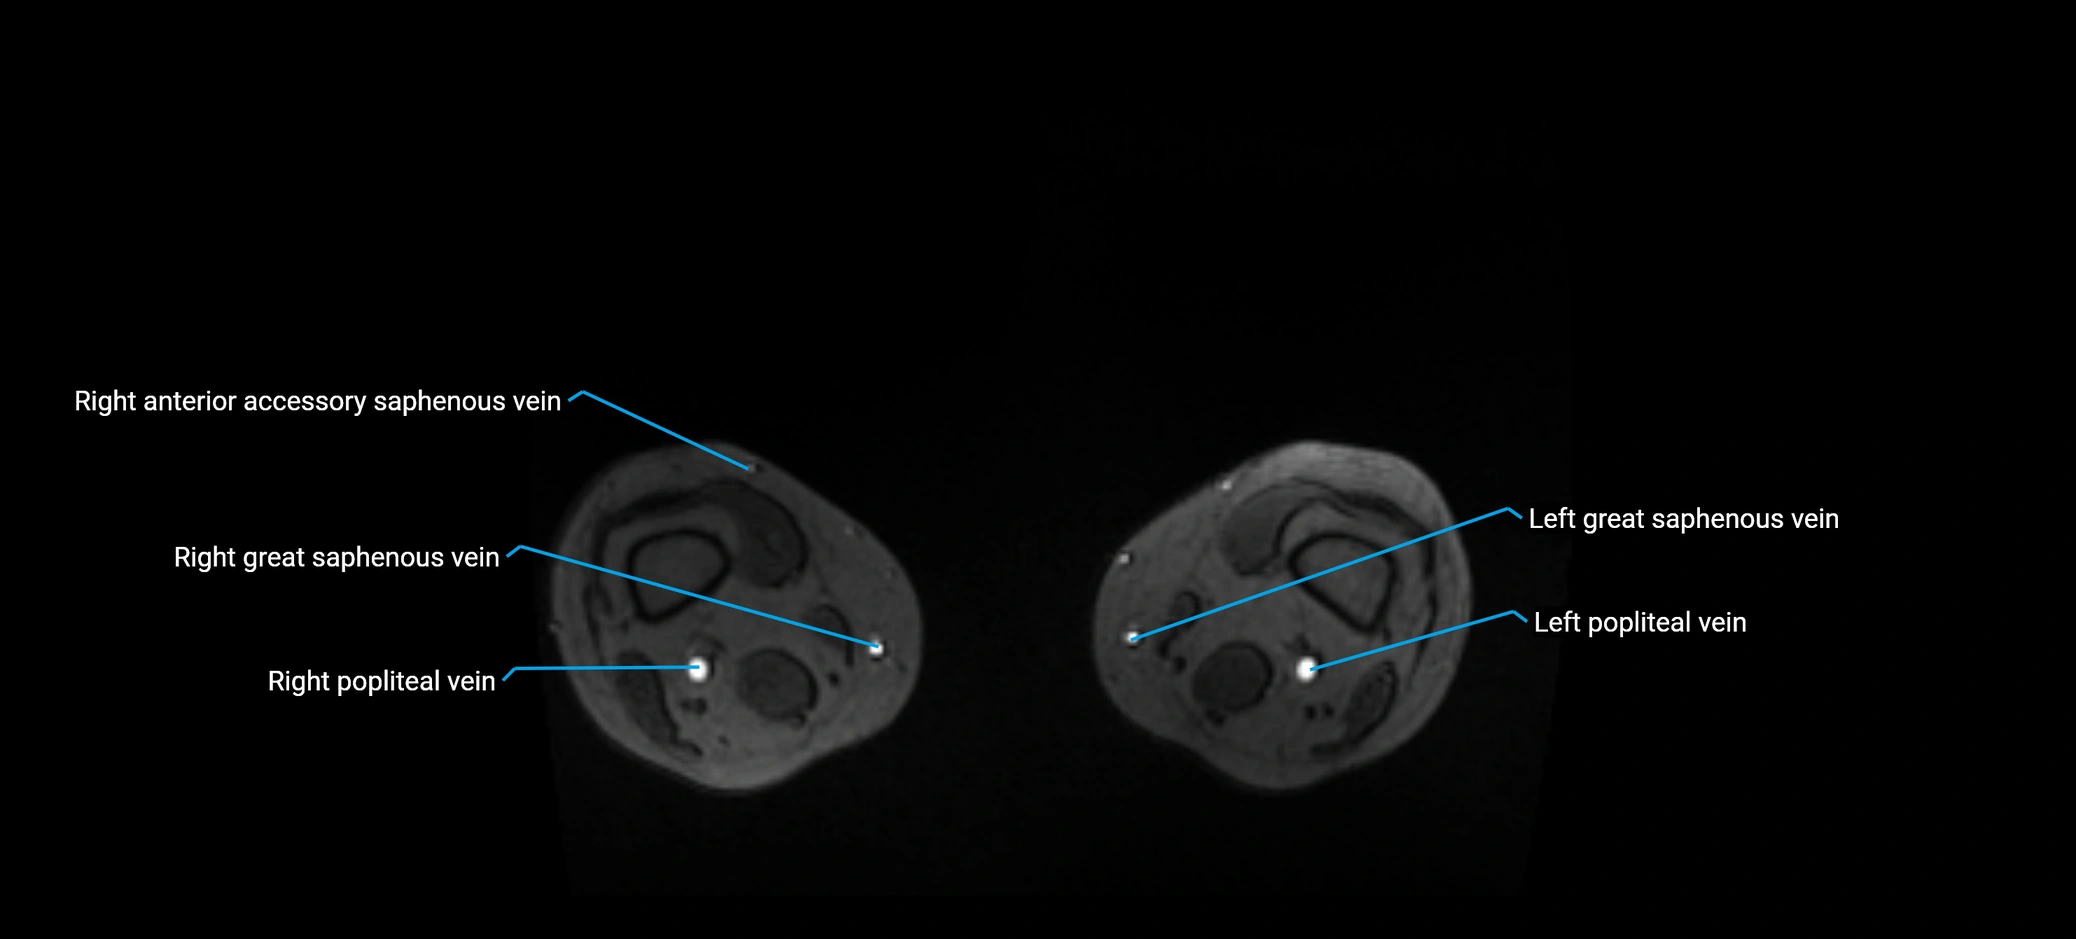

MRI image

image